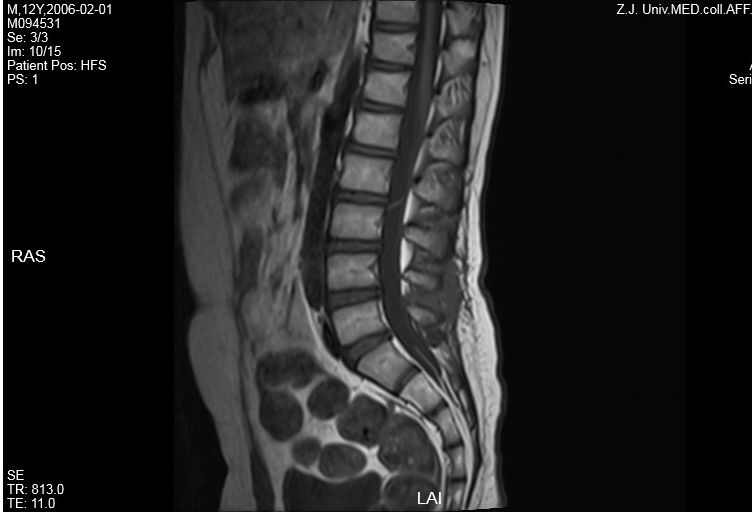

头颅MR:左侧小脑半球异常信号,左侧脑室体部后外侧异常信号,双侧半卵圆中心、侧脑室旁血管周围间隙增多。颈胸髓及腰骶部MRI提示:C3-T4平面脊髓肿胀,伴多发异常信号,胸髓全段肿胀,伴信号异常,腰骶髓异常信号影,考虑脊髓炎可能(图1)。

图1. 第一次住院头颅及脊髓MRI,显示左侧小脑半球异常信号。脊髓全段肿胀,伴信号异常,腰骶髓异常信号影,考虑脊髓炎可能。